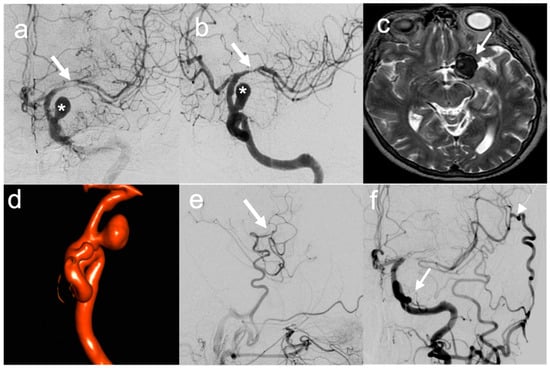

- In three patients (patients no. 10, 15 and 18), a side-to-side pericallosal artery–pericallosal artery (perA–perA) bypass was performed to preserve distal flow in the ACA territory, before endovascular treatment of complex aneurysm in the proximal ACA (Figure 4).